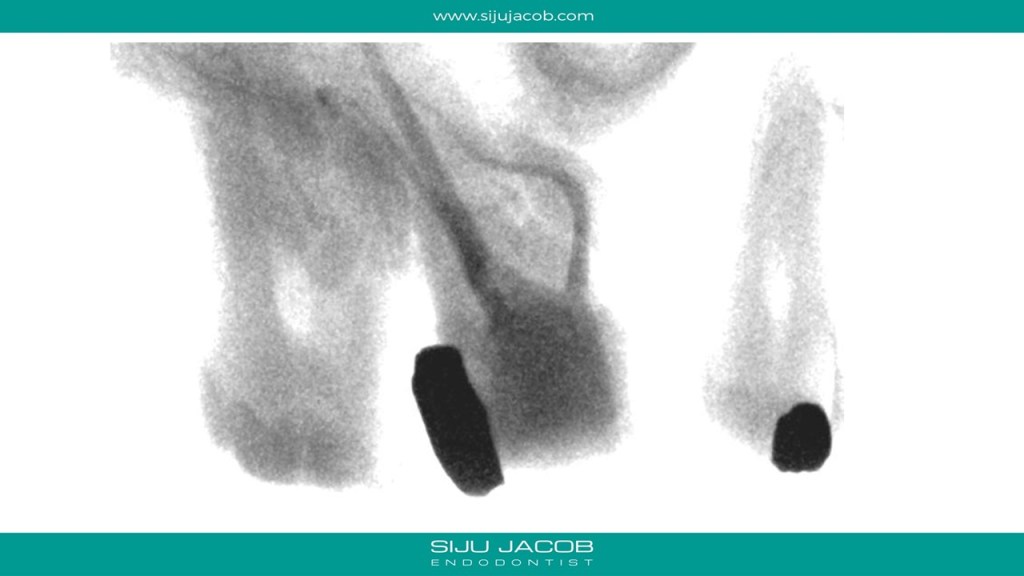

The Mesio-buccal canal in this tooth was probably the most curved canal I ever treated. It went straight initially, then took a left turn, then a right, then a left again to exit. And to add to the Drama, it was before Christmas holidays and the palatal root ended up with sealer pushed apically in the shape of a proper Christmas Star. Bizarre! π